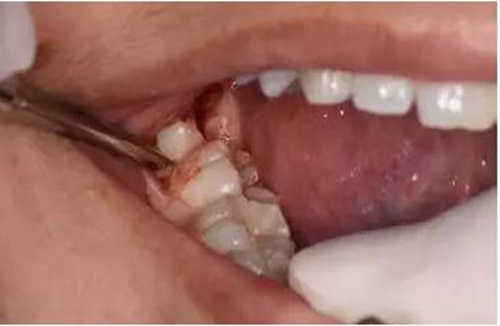

圖3.術(shù)前的口內(nèi)觀:48看不到,47遠(yuǎn)中有深盲袋、可探及48牙冠

圖6. 從37頰側(cè)中份齦溝內(nèi)開始切開,向磨牙后區(qū)延伸

圖9.翻小瓣、用骨膜剝離器輕柔牽拉頰側(cè)齦瓣、暴露48合面